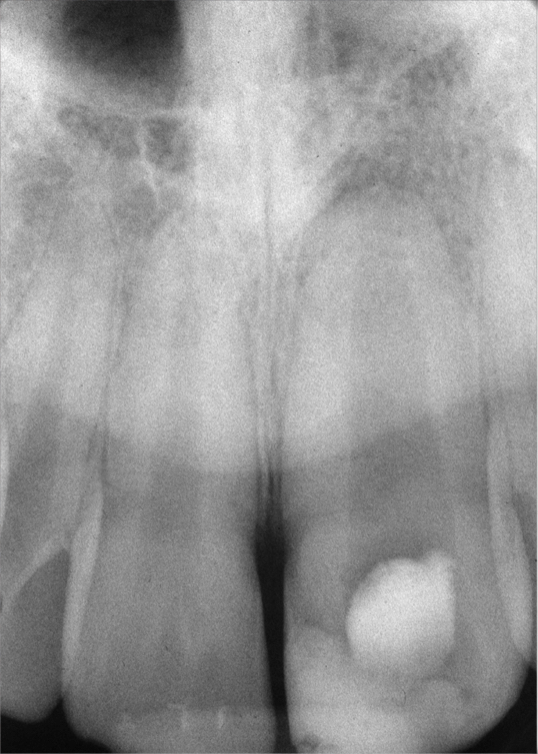

Fig 4. Preoperative radiograph showing aggressive external root resorption and thin dentinal walls.

Figure 4